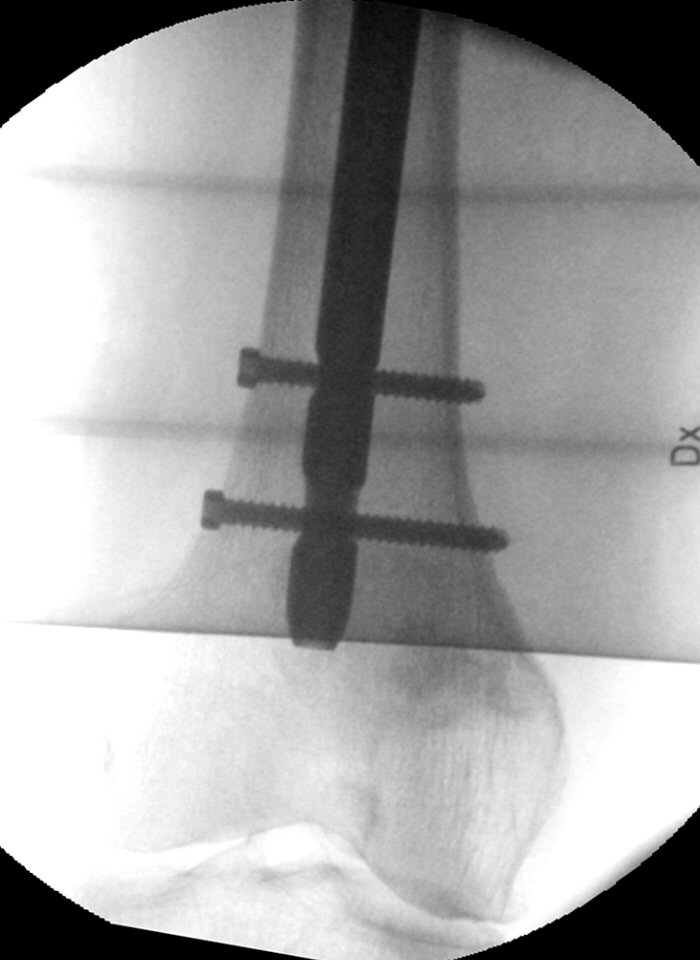

- Skruva in skruvarna "lagom" hårt, se till i genomlysning att de hamnar rätt. Om de går alltför trögt, skruva ut och borra igen, låt borren “vandra runt” lite.

- Lagra peroperativa bilder om det inte är gjort tidigare.

Lagom lång gammaspik med bra läge på glidskruv, lagom långa låsskruvar varav en statisk och en dynamisk